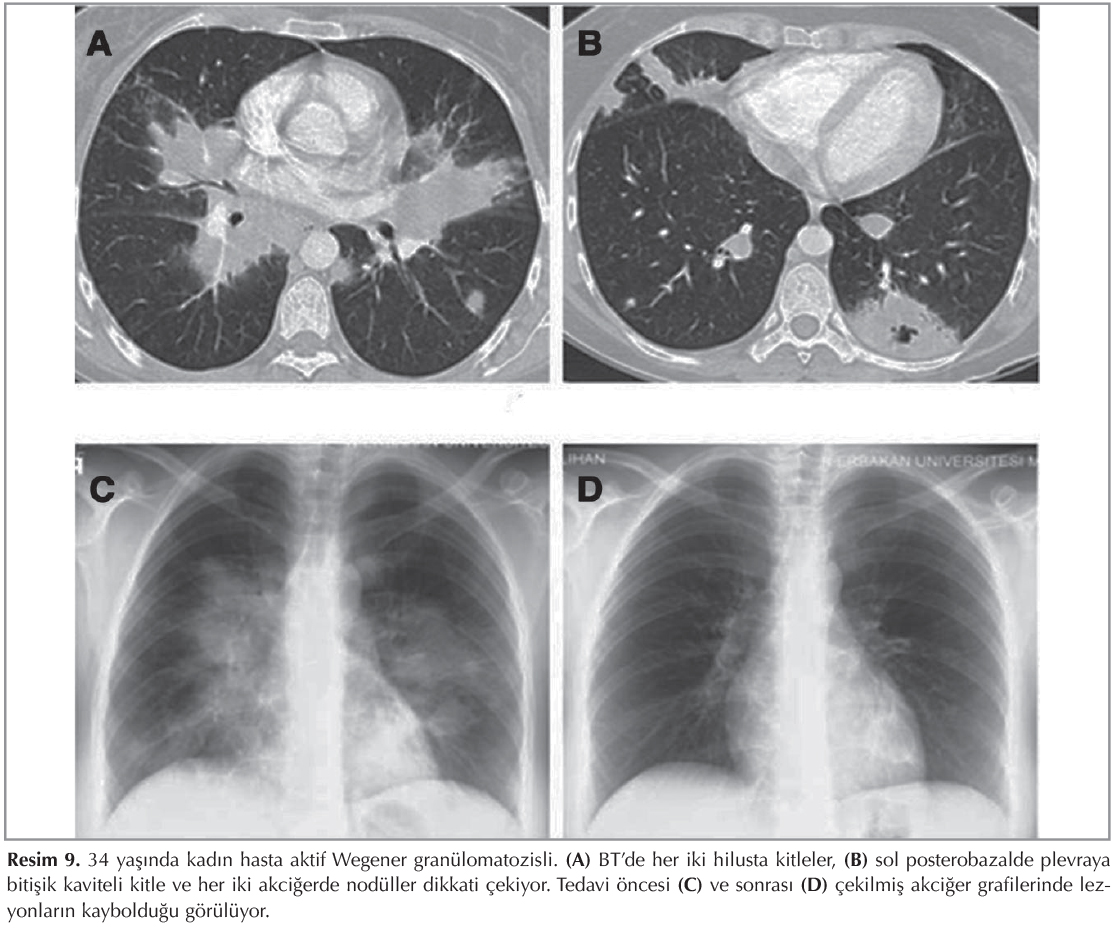

WG takip s?recinde yeni kitle ve nod?ller ortaya ?ıkabilir (Resim 8). Nod?ller tedavi edilmezse b?y?yebilir veya kaviteleşebilir; tedavi edildiği zaman genellikle kaybolur ya da skar dokusu ile iyileşir (Resim 9). WG hastalarında malignite riski iki kat artmış olduğu i?in klinik veya imm?nolojik testlerle tanısı doğrulanamayan ş?pheli nod?llere mutlaka biyopsi yapılmalıdır (6).?

Resim 9

Tedavi sonrası kontrol BT'de olguların ?oğunda parankimal lezyonların tama yakın kaybolduğu g?r?l?r, fakat bazı hastalarda tekrar n?ks g?r?lebilir (Resim 9) (8,10,13).